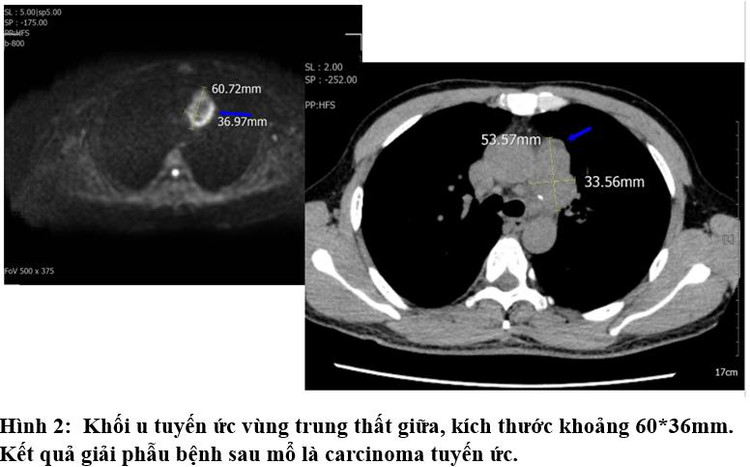

Tại đây, kết quả chụp CT toàn thân của bệnh nhân M. ghi nhận có khối u tuyến ức ở vùng trung thất giữa, với kích thước khoảng 60*36mm. Mẫu giải phẫu bệnh sau phẫu thuật cho thấy khối u tuyến ức ở vùng trung thất giữa của bệnh nhân M. là ung thư tuyến ức (thymic carcinoma). Các bác sĩ đã nhanh chóng hội chẩn để đưa ra các giải pháp điều trị kịp thời cho bệnh nhân M.

![]() |